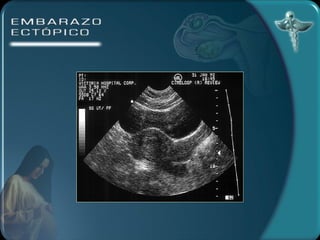

DIAGNÓSTICO Por imagen Ecografía transvaginal útero vacío 100% tumor parauterino 85 % embrión 55% Anillo tubárico Líquido en el fondo del saco

DIAGNÓSTICO Por imagenEcografía transvaginal útero vacío 100% tumor parauterino 85 % embrión 55% Anillo tubárico Líquido en el fondo del saco

• #23 DIAGNÓSTICO )LABORATORIO: la hemoglobina y el hematocrito pueden ser de utilidad para el seguimiento de la paciente. Estos valores pueden no alterarse precozmente ante una hemorragia.La leucocitosis puede estar presente en el 50% de los casos mientras que el otro 50% permanece con valores normales.La gonadotrofina coriónica humana puede investigarse en suero o en orina. Las pruebas urinarias son de poca sensibilidad en esta patología. Con la prueba de ß HCG en suero se puede detectar todo tipo de embarazos. Los niveles de la ßHCG se correlacionan con la edad gestacional. Durante las primeras 6 semanas de gestación los niveles séricos se incrementan en forma exponencial ( la duplicación del valor de la ßHCG es constante), después de las 6 semanas (nivel de la ßHCG de 6000 a 10000 mUI/ml) el ascenso se hace más lento y menos constante. Cundo los niveles de ßHCG son bajos (por debajo de 1000 mUI/ml) el valor absoluto es menos útil para diferenciar un embarazo normal de uno extrauterino. 2) ECOGRAFÍA TRANSABDOMINAL A) ÚTERO VACÍO B) MASA ANEXIAL C) LÍQUIDO EN EL FONDO DE SACO Con este método no es posible diagnosticar embarazos pequeños de 5 a 7 semanas. 3) ECOGRAFÍA TRANSVAGINAL A) ANILLO TUBÁRICO: un anillo ecogénico alrededor de un centro hipoecogénico como estructura encontrada fuera del útero. B) LÍQUIDO EN EL FONDO DE SACO Este método permite un diagnóstico precoz del embarazo ectópico 4) CULDOCENTESIS: se realiza cuando se detecta una colección líquida en el saco de Douglas. 5) LAPAROSCOPÍA: permite establecer el diagnóstico definitivo.